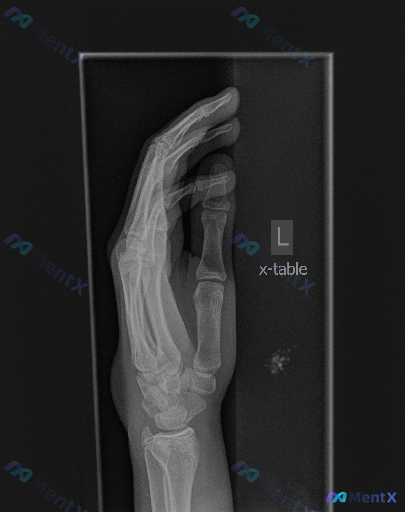

大家好,今天我们来讨论一张左手的X线片。这是一张左手侧位/斜位投照的影像,曝光适中,骨皮质轮廓清晰。首先和大家同步一下影像的基础表现: 1. 骨骼方面:第1-5掌骨、近中节指骨及可见腕骨区域,均未见明确的骨皮质中断、骨折线或关节脱位征象,骨骺线已闭合,各关节对位良好、间隙清晰,也未见明显的骨赘形成。...